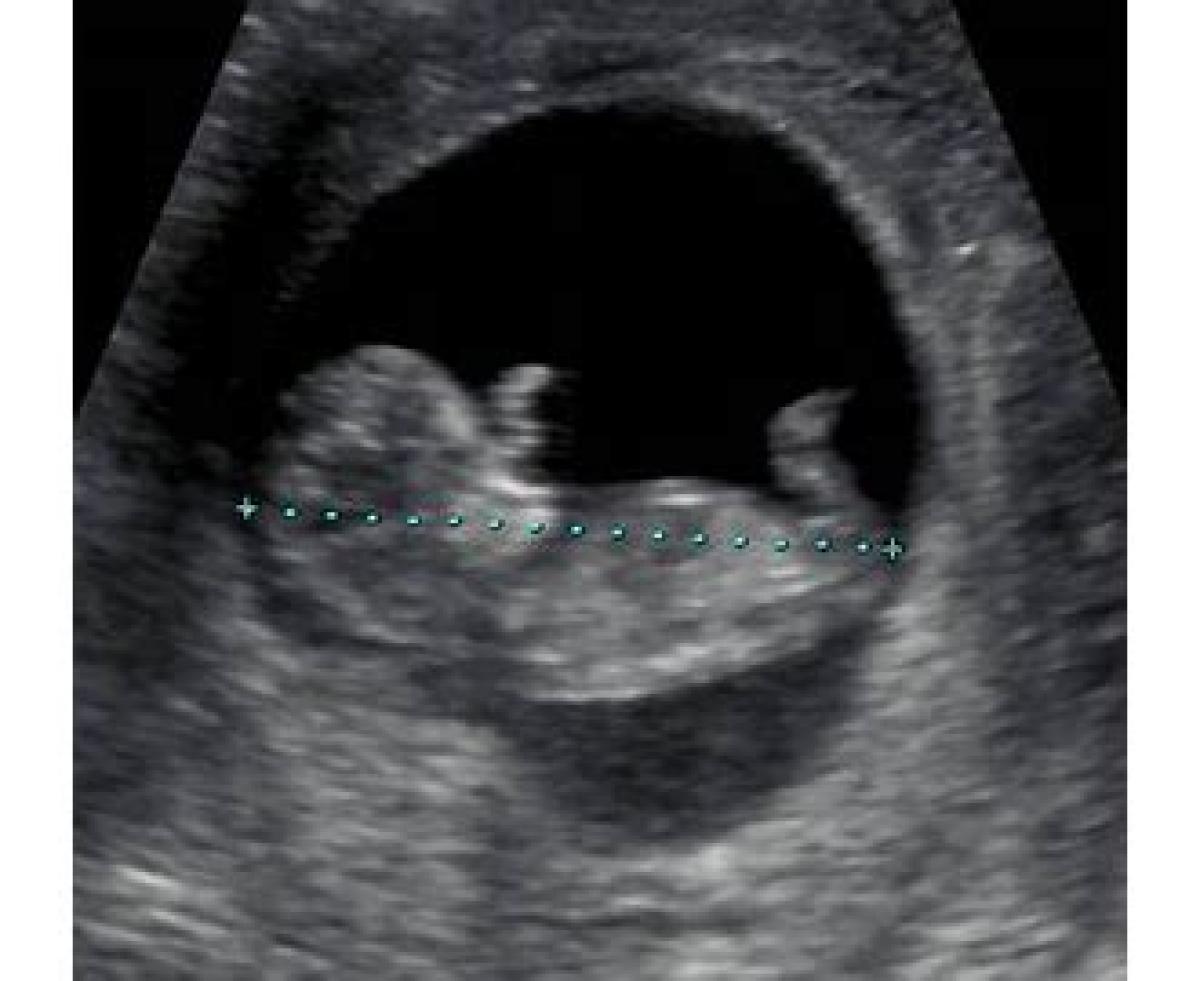

مخفف CRL Crown-Rump Length CRL به معنی طول طلایی و اندازه طول بالا تنه جنین است. در واقع اندازه سر جنین تا کفل آن را تعیین می کند. اندازه گیری این پارامتر از هفته ششم تا هشتم به بعد انجام شده و می توان تاریخ زایمان را با آن مشخص کرد.مشاهده نسخه کامل